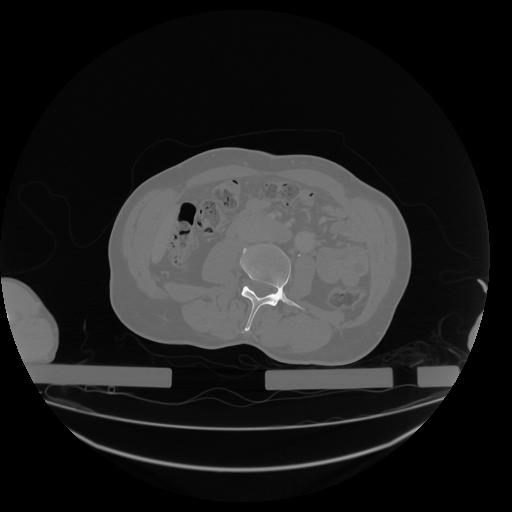

34 CUERPO,CE,Vol,1.0,CUERPO,,